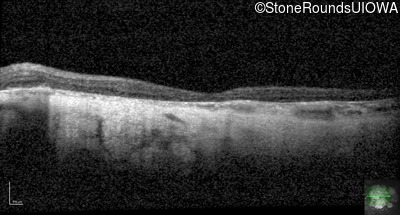

Age at visit: 43 years

OD OS